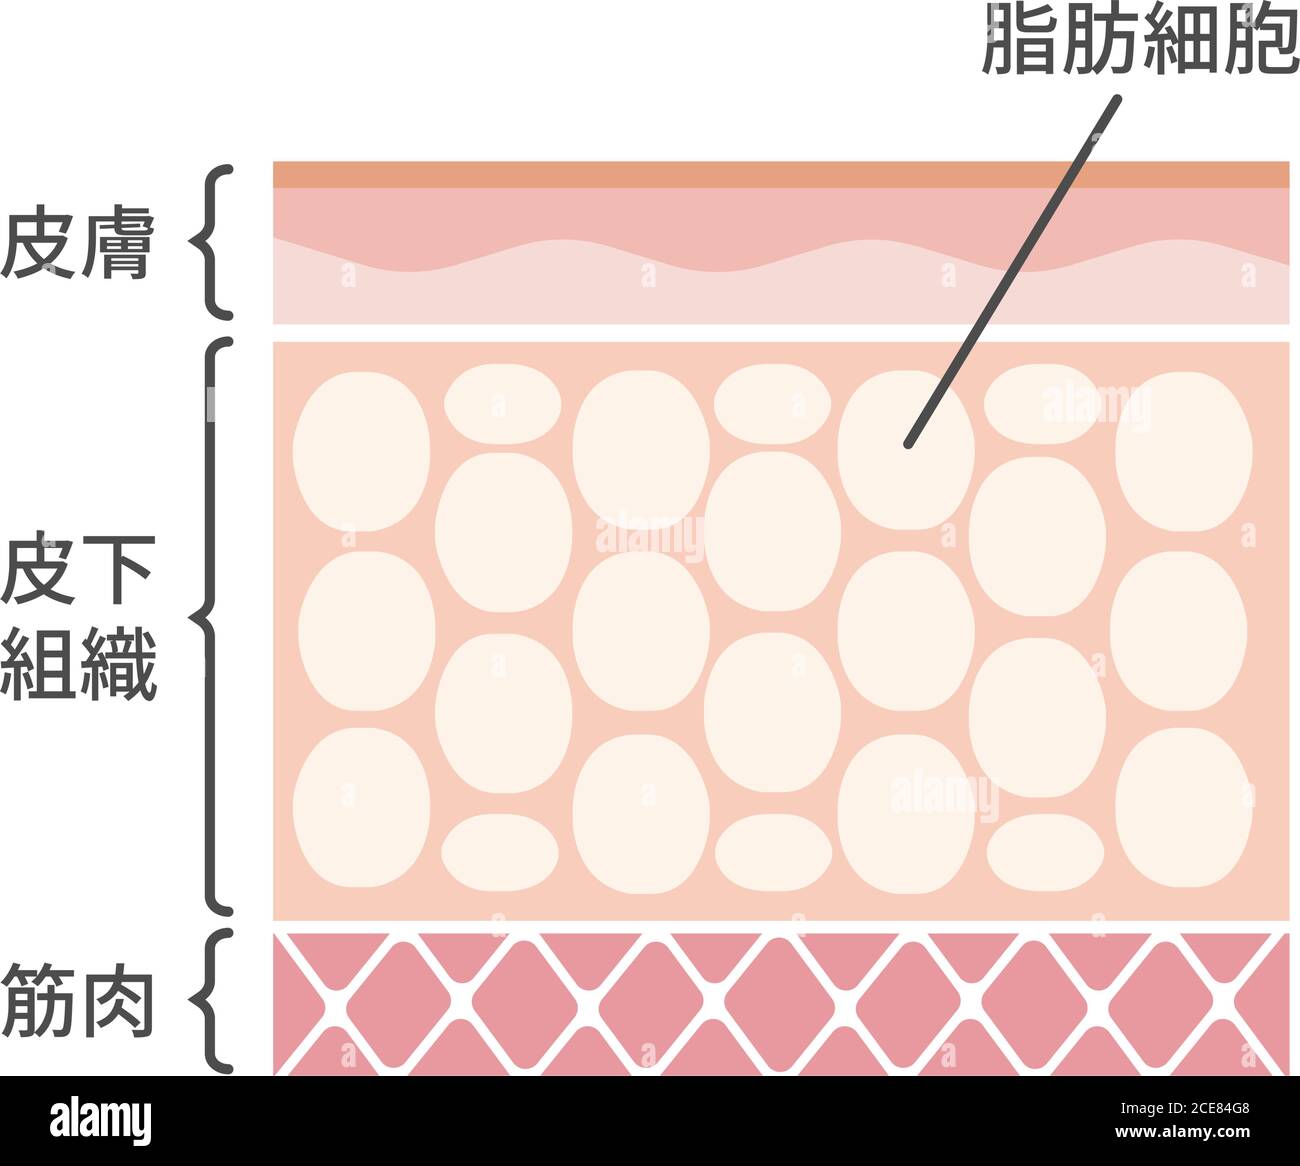

Illustration vectorielle du processus de liposuccion / vue en coupe de la peau Illustration de Vecteurhttps://www.alamyimages.fr/image-license-details/?v=1https://www.alamyimages.fr/illustration-vectorielle-du-processus-de-liposuccion-vue-en-coupe-de-la-peau-image370202117.html

Illustration vectorielle du processus de liposuccion / vue en coupe de la peau Illustration de Vecteurhttps://www.alamyimages.fr/image-license-details/?v=1https://www.alamyimages.fr/illustration-vectorielle-du-processus-de-liposuccion-vue-en-coupe-de-la-peau-image370202117.htmlRF2CE84G5–Illustration vectorielle du processus de liposuccion / vue en coupe de la peau

vue en coupe de l'illustration du vecteur des cellules graisseuses Illustration de Vecteurhttps://www.alamyimages.fr/image-license-details/?v=1https://www.alamyimages.fr/vue-en-coupe-de-l-illustration-du-vecteur-des-cellules-graisseuses-image370202120.html

vue en coupe de l'illustration du vecteur des cellules graisseuses Illustration de Vecteurhttps://www.alamyimages.fr/image-license-details/?v=1https://www.alamyimages.fr/vue-en-coupe-de-l-illustration-du-vecteur-des-cellules-graisseuses-image370202120.htmlRF2CE84G8–vue en coupe de l'illustration du vecteur des cellules graisseuses

Graisse viscérale et inflammation chronique. Coupe transversale de l'abdomen féminin avec muscle abdominal, graisse sous-cutanée et viscérale. Gros plan de tiss adipeux Illustration de Vecteurhttps://www.alamyimages.fr/image-license-details/?v=1https://www.alamyimages.fr/graisse-viscerale-et-inflammation-chronique-coupe-transversale-de-l-abdomen-feminin-avec-muscle-abdominal-graisse-sous-cutanee-et-viscerale-gros-plan-de-tiss-adipeux-image608706238.html

Graisse viscérale et inflammation chronique. Coupe transversale de l'abdomen féminin avec muscle abdominal, graisse sous-cutanée et viscérale. Gros plan de tiss adipeux Illustration de Vecteurhttps://www.alamyimages.fr/image-license-details/?v=1https://www.alamyimages.fr/graisse-viscerale-et-inflammation-chronique-coupe-transversale-de-l-abdomen-feminin-avec-muscle-abdominal-graisse-sous-cutanee-et-viscerale-gros-plan-de-tiss-adipeux-image608706238.htmlRF2XA8Y0E–Graisse viscérale et inflammation chronique. Coupe transversale de l'abdomen féminin avec muscle abdominal, graisse sous-cutanée et viscérale. Gros plan de tiss adipeux